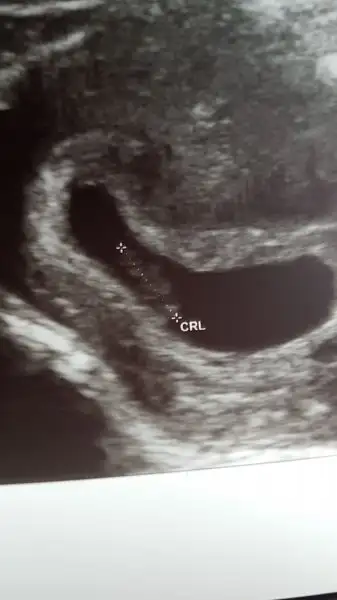

Canım benim son adet tarihim 27 ekim. 8+1 olmam lazım ama regli döngüm kısa olduğu ve ultrason görüntüsü dikkate alınarak 23 ekim olarak güncelledi doktorum kayıtlarımı, erken döllenme yani. Mantar için vajinal duş ve fitil verdi.